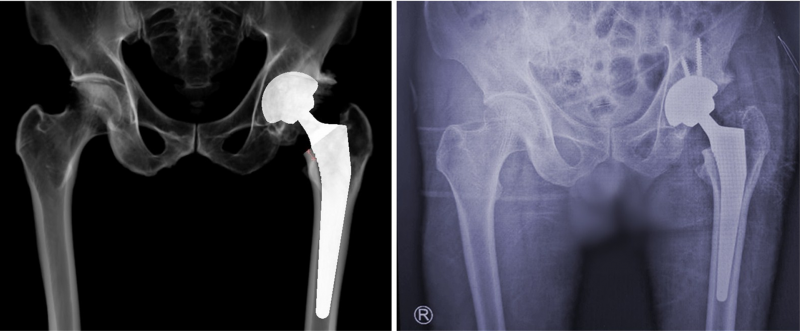

当日,骨关节科医生通过术前精细规划,预知了手术中的情况,加以精湛的手术操作,完成了这台人工智能辅助初次全髋关节置换术,达到了预期手术效果,术后真实的X线影像结果也与术前模拟的X线影完全吻合。

术前规划模拟X线影像与手术后实际X线影像完全吻合